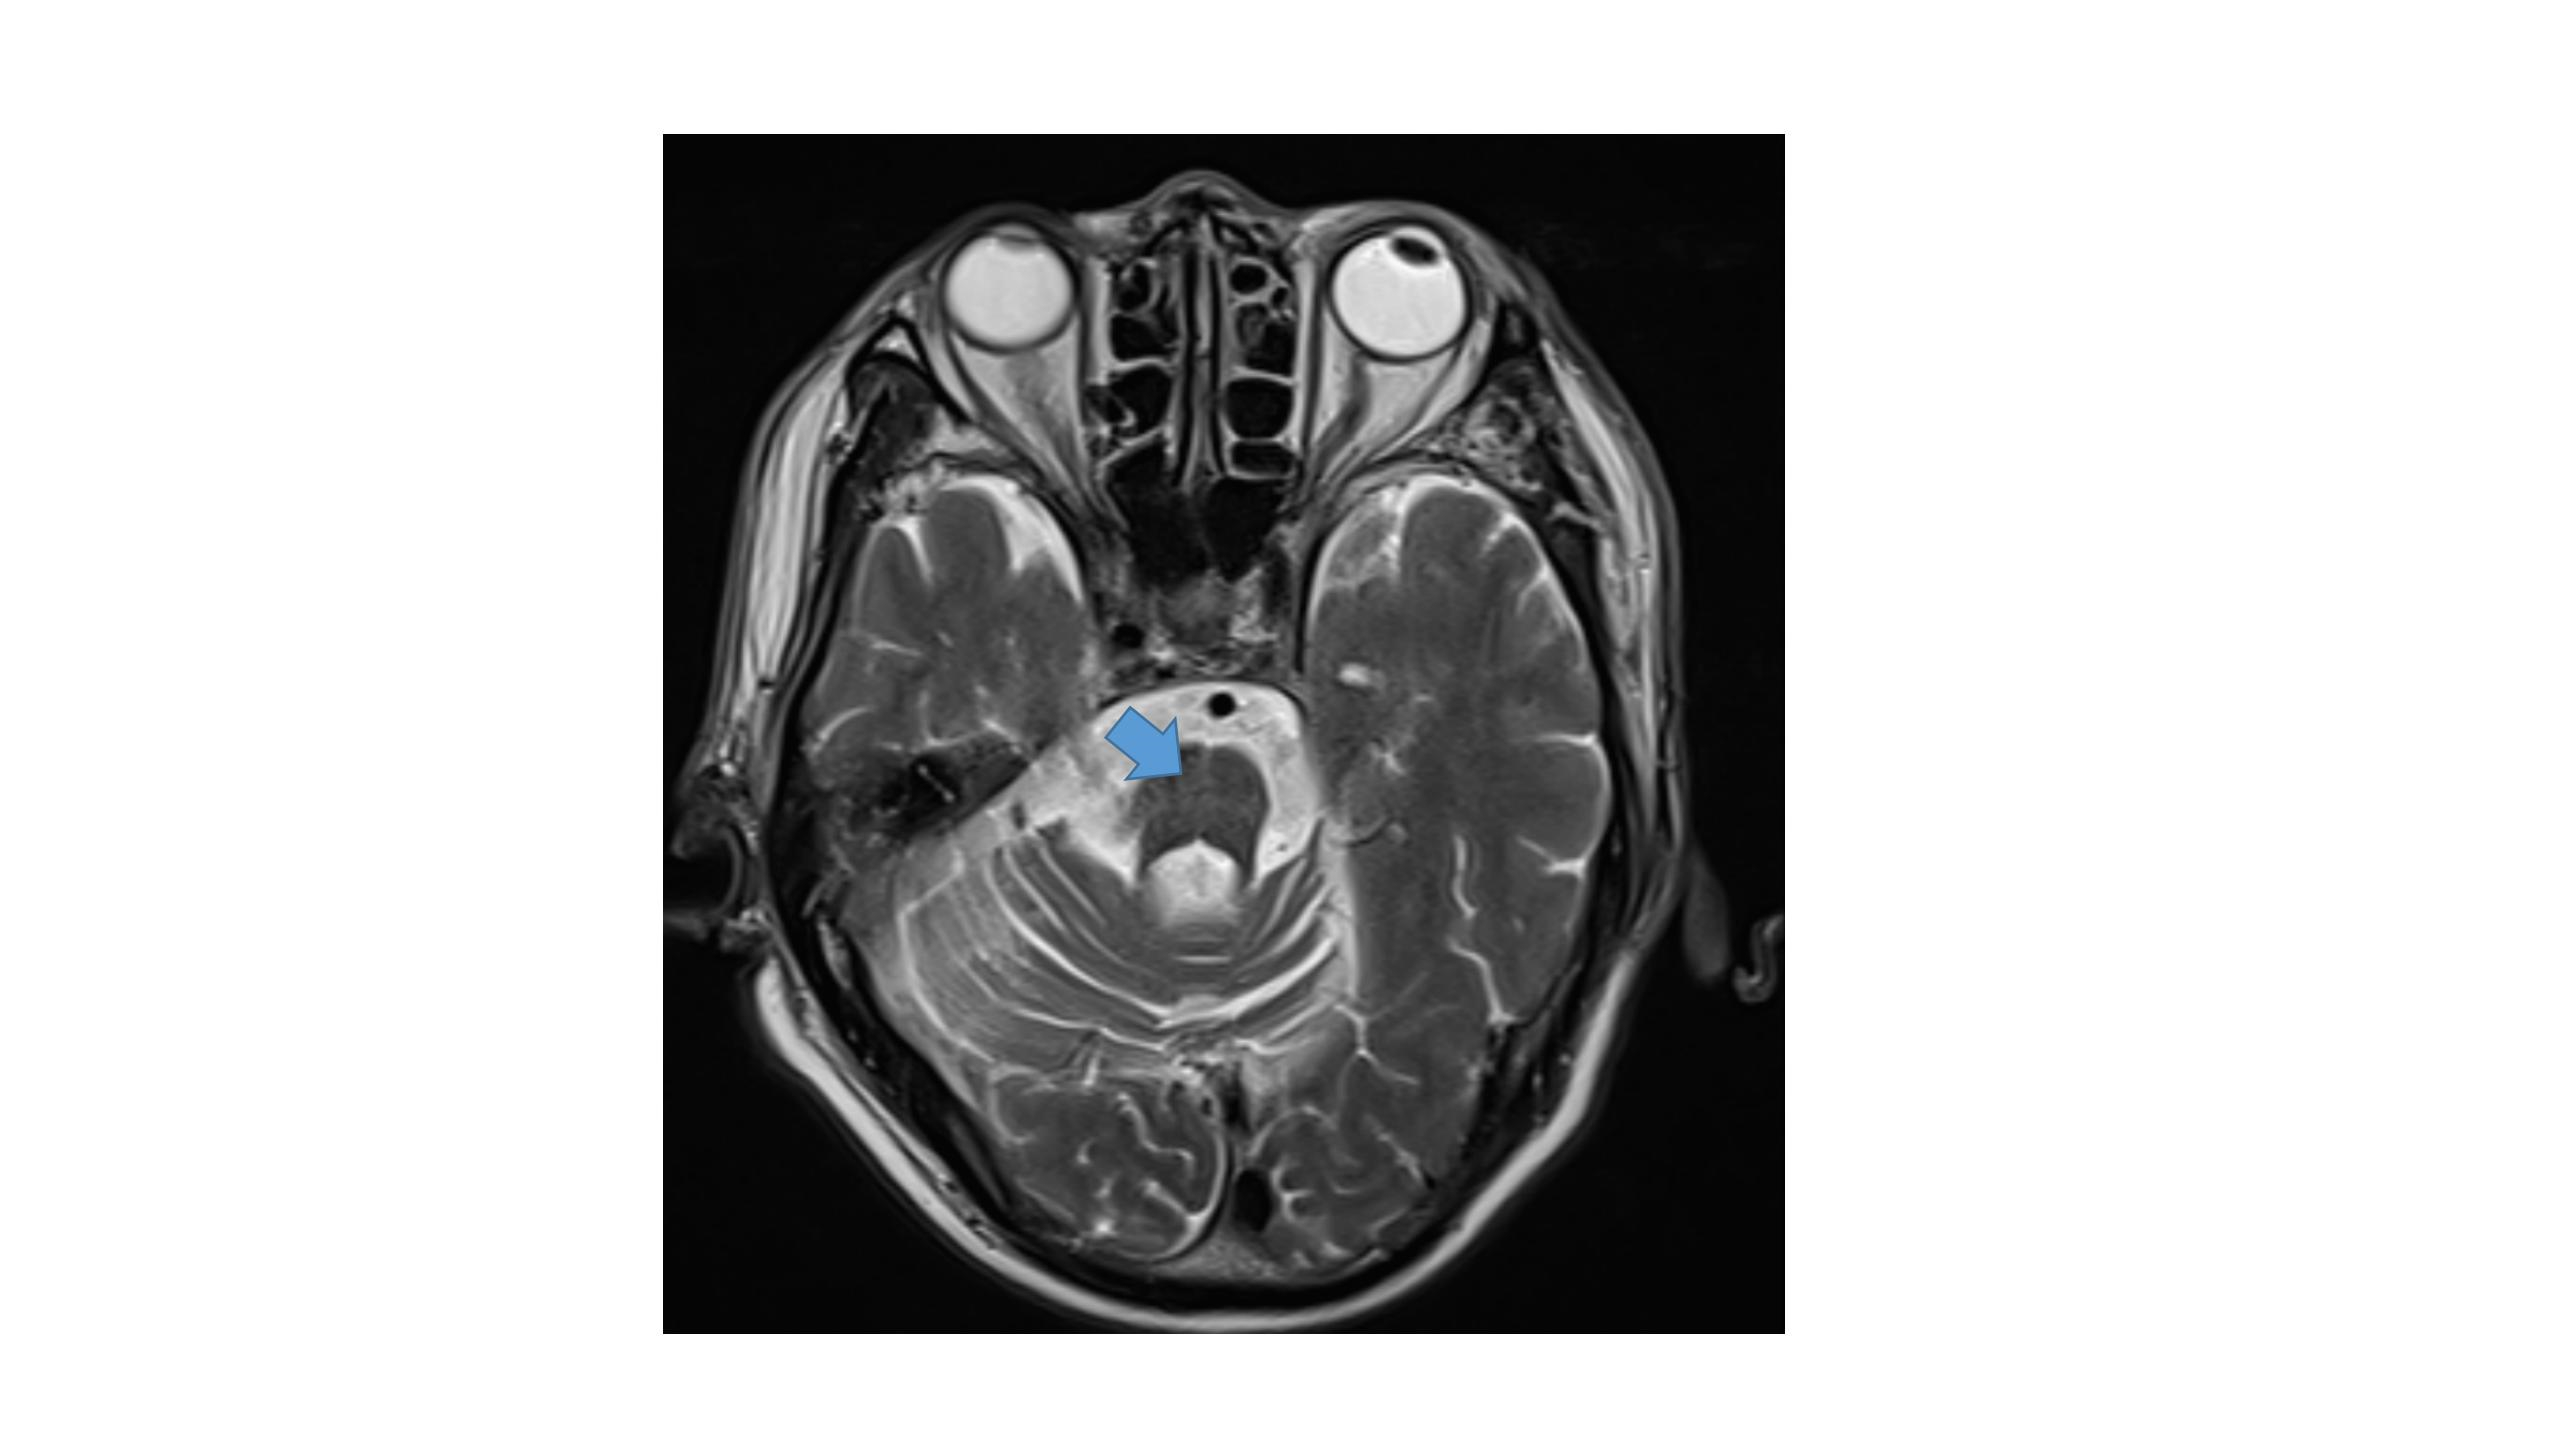

入院查体:体温36.9℃,脉搏56次/min,呼吸20次/min,血压120/60 mmHg。神清,精神差,言语含混,急病面容,平卧位,查体合作。双侧瞳孔等大、等圆,对光反射灵敏,眼睑正常,结膜正常,巩膜无黄染,双下肺呼吸音低,未闻及明显干、湿啰音,心音正常,律齐,心率56次/min,各瓣膜听诊区未闻及病理性杂音。腹部平软,无压痛及反跳痛,双侧下肢无水肿。四肢肌力4级+,肌张力稍高,双侧巴彬斯基征阳性。既往心动过缓病史多年,未系统诊治。否认其他慢性疾病史,否认新冠肺炎疫区居住、工作史,否认新冠肺炎确诊、疑似患者接触史,患者新冠肺炎病毒核酸检测阴性。否认药物过敏史,个人史、家族史无特殊。入院诊断:①晕厥原因待查疑似急性脑血管病;②肺炎;③脓毒症;④横纹肌溶解症;⑤多器官功能障碍综合征;⑥心动过缓。诊治经过:入院后查血生化示:CK、CK-MB、MYO、TNI、ALT、AST、TBIL、CR显著升高,并随时间延长动态改变(见图 1~2)。血常规:WBC 3.2×109/L,HGB 131 g/L,PLT 120×109/L,中性粒细胞百分比77.2%;凝血常规:凝血酶原时间14.10 s,INR 1.25,凝血酶原百分活度74%,纤维蛋白原4.57 g/L,D-二聚体2 270.29 μg/L;C-反应蛋白63.73 mg/L;PCT 0.65 ng/mL;甲状腺功能:TSH 7.94 mIU/L,TT3、FT3、TT4、FT4、Anti-Tg、TPO-Ab正常;风湿系列、免疫全项、肿瘤标志物、抗核抗体系列、超声心动、腹盆CT未见异常。头MRI+SWI+flair(2022-08-11):双侧半卵圆中心急性腔隙性梗死;脑桥、小脑、橄榄及中脑体积减小,脑桥“十字征”,考虑多系统萎缩(见图 3)。给予阿莫西林克拉维酸钾抗感染、甲强龙抗炎平喘、优甲乐补充甲状腺素,对症补液、利尿、碱化尿液、保肝等治疗。入院第2天开始患者尿量较前明显增多,3 000 mL/d,尿色渐正常,乏力及肌肉疼痛较前好转,复查尿常规正常、尿蛋白阴性,CK、CK-MB、MYO、CR等生化指标持续下降。入院第3天患者头MRI提示多系统萎缩,详细追溯病史,患者自10年前渐进出现行走不稳、动作迟缓、声音较前含混,吐字不清晰,小便时有尿频尿不尽,平日变换体位直立时偶有头晕。患者腹盆CT结果除外前列腺增生,尿常规除外泌尿系感染,结合病史、发病特点及影像学结果,根据2008年Gilman等[1]提出的诊断标准及2023年《多系统萎缩诊断标准中国专家共识》[2],诊断为“临床确诊的MSA”。入院第14天患者症状及各项化验指标明显好转出院,2周后门诊复查各项生化指标完全恢复正常。出院诊断:①横纹肌溶解症;②肺炎;③脓毒症;④多器官功能障碍综合征;⑤系统萎缩;⑥亚临床甲减。

| 图 3 患者头部MRI T2WI见脑桥“十字征” |

本例老年男性患者,独自高温劳作时突发晕厥,待家属发现后送医,持续时间约为3 h,患者病程中体温正常,可除外热射病,结合化验检查结果考虑肺炎、脓毒症、横纹肌溶解症、多脏器功能障碍,晕厥原因考虑为肺炎所致脓毒性脑病。入院后完善头MRI提示多系统萎缩,追溯病史结合患者发病特点及临床表现支持“临床确诊的MSA”诊断,MSA-C亚型可能性大。患者自10年前渐进出现行走不稳、动作迟缓,自述此次发病时曾多次摔倒,伴头晕,此次发病亦不除外MSA自主神经功能障碍所致体位性低血压所致。

MSA是一种成年发病的、致死性的神经退行性疾病。脑病理可见少突胶质细胞胞浆内α-突触核蛋白阳性的嗜酸性包涵体(GCI),并伴有橄榄、脑桥、小脑萎缩或黑质纹状体变性[3-4]。MSA为临床罕见病,患病率3.4/100 000~4.9/100 000,40岁以上人群患病率升高至7.8/100 000,通常60岁以后发病[5]。目前无确切已知病因,通常为散发。临床表现主要包括帕金森症、小脑性共济失调、锥体束损害以及自主神经系统损害。首发症状常为自主神经损害,最主要的是心血管功能障碍(如直立性低血压)和排尿障碍(如尿失禁)。依据主要运动症状分为两个亚型:即以帕金森症为主要表现的MSA-P型和以小脑性共济失调为主要表现的MSA-C型。头MRI是常用的检查手段。MSA患者的典型MRI特征包括:①脑桥萎缩,出现“十字征”;②壳核裂隙征;③小脑萎缩。